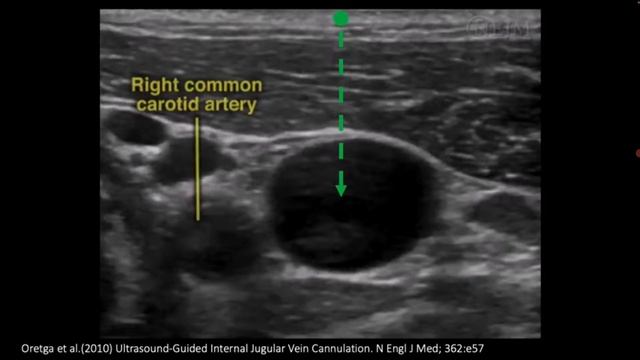

Установка катетеров в вену, видео от 2026-01-04 загрузил на rutube УЗИ обучение @dr.molov...